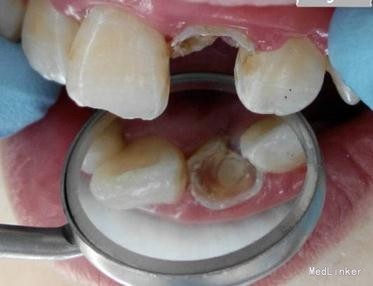

检查:21 自凝树脂桩核修复,树脂冠略有松动,叩诊无明显不适,唇侧牙龈有一陈旧性瘘管。

X-ray显示根管治疗不完善。

诊断:21不良修复体